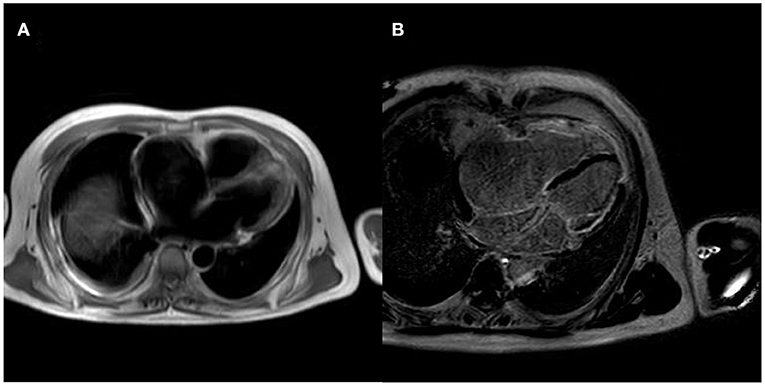

After controlling the patient's heart rate with medication, a cardiac magnetic resonance examination was performed. The result of magnetic resonance imaging (MRI) (Figure 3) showed that the left atrial and left ventricular internal diameters were normal, the right atrium was 61 mm anterior-posterior, and the right ventricular transverse diameter was 43 mm. The delayed scan showed diffuse striated enhancement of the left ventricular lateral wall, apex of heart, and right ventricular wall, with some transmural enhancement, LVEF 35%, and cardiac output 2.61 L/min.

Figure 3. MRI of the patient's heart [(A) is a whole heart cross-sectional view, which shows a small left atrium and an enlarged right atrium; (B) is a delayed scan, which shows diffuse strip enhancement of the left ventricular lateral wall, apical region, and right ventricular wall, with some transmural-like enhancement].

Echocardiography and cardiac MRI can clarify the extent and degree of myocardial disease and quantitatively assess cardiac function. Desmin myopathy often presents as different types of cardiomyopathy, including dilated cardiomyopathy, hypertrophic cardiomyopathy, restrictive cardiomyopathy, arrhythmogenic right ventricular cardiomyopathy, and non-dense cardiomyopathy (7, 8). Arrhythmias include atrioventricular block, bundle branch block, atrial fibrillation, and ventricular tachycardia (9). CMR can differentiate between injured and normal myocardium. T2-weighted imaging sequences of myocardial hyper-signal reflect myocardial edema, and perfusion sequences can detect myocardial ischemia (10). The echocardiogram showed severe right heart damage, consistent with restrictive cardiomyopathy. Still, the cardiac MRI showed that the left ventricular myocardium was also involved, and the LVEF value was significantly reduced. In this case, the right atrium was dilated, resulting in right atrial remodeling, which facilitated the formation of a foldback loop, resulting in rapid atrial pulsation, and eventually atrial flutter. On the contrary, the loss of atrial pump function and the desynchronization of atrial and ventricular motion during atrial flutter can further induce and aggravate heart failure, creating a vicious circle between the two, and significantly reducing activity tolerance. In addition, junctional proteins are also expressed in Purkinje fibers and intercalated discs; therefore, junctional protein myopathy often causes conduction block arrhythmias (11). In this case, the electrocardiogram shows a non-specific intraventricular block, suggesting an involvement of the cardiac conduction system. If the lesion worsens, a complete AV block at the branch level may occur, leading to syncope or sudden cardiac death.